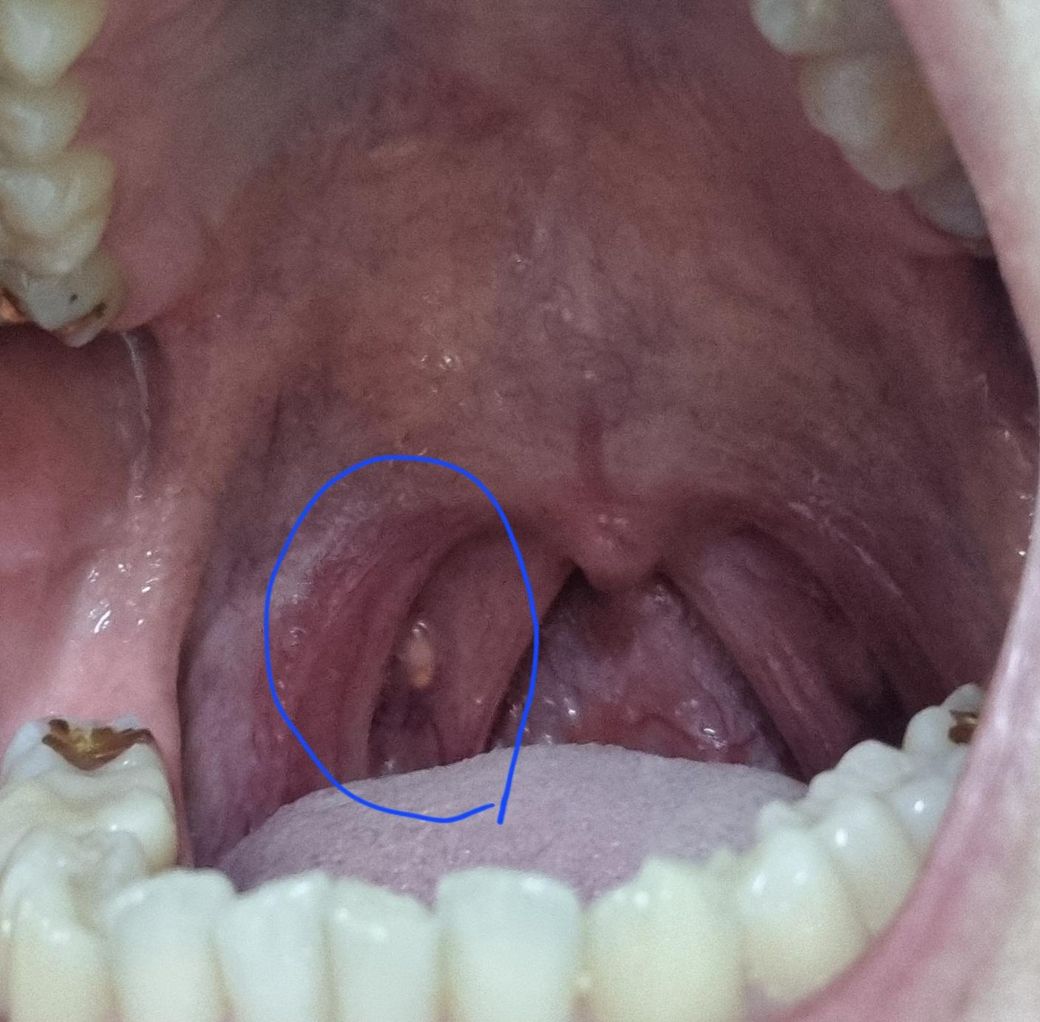

목구멍 안이 하얗게 돋아난 무엇인가를 어떻게 봐야할까요?

몇년전부터 있었긴 힙니다.

감기 1주일차에 목이 잘 안낫는거같아서 상태보려고 목안을 봤는데

저게 유독 신경쓰이네요.

혹시 저거 뭔지 알 수 있을까요??

• 1번 째 사진

사진으로는 오른쪽 편도 결석이 의심되는 상태로 결석이 있는 경우,

빠져나오지 않는 경우, 주변으로 염증과 통증을 반복적으로 유발할 수

있습니다. 항생제 처방과 함께 따뜻한 음료를 마시고 호전이 없는 경우,

이비인후과 진료를 통해 시술을 통해 제거하는 것이 좋을 것으로

보입니다.

일단 병변이 작아서 정확한 진단을 하기는 어려우나 가능성이 있는 것으로는 편도에 음식물의 찌꺼기나 세균등이 침착하면서 생긴 편도결석일 가능성이 있어 보입니다. 만약 구취나 이물감이 있는 경우라면 편도 결석을 생각해 봐야 할 수 있어서 이비인후과에 방문하셔서 의사의 진찰을 받으시기 바랍니다.